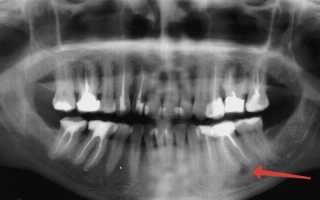

Киста может располагаться в любой части ротовой полости. Ее развитие происходит медленно, начиная с воспаленного очага, который приводит к образованию полости, заполненной гноем. Диагностировать кисту на этом этапе можно только с помощью рентгена или в процессе лечения других заболеваний десен и зубов, таких как гингивит, кариес, пульпит и пародонтоз.